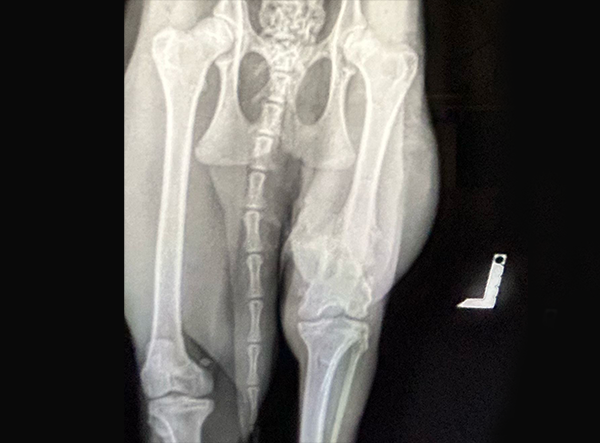

In April 2025, a stunning caracal suffering from a femur fracture began its road to recovery — and is now on its way to roaming freely in the wild.

The femur fracture was surgically treated by Dr. Matan Or, using a 3.5 LeiLOX Locking Bridge Plate to provide stable fixation and support the healing process. The LeiLOX system is designed to offer reliable stability while minimizing soft tissue disruption, which is crucial for optimal recovery and a safe return to natural mobility. Its locking mechanism ensures strong fixation, and the bridging technique helps maintain blood supply to the bone, supporting natural bone regeneration.

Since the operation, the caracal has been recovering well, with stable post-op results and steady healing progress. Although a full recovery will take time, the outlook is very encouraging, and the wild cat is expected to gradually regain strength and mobility.